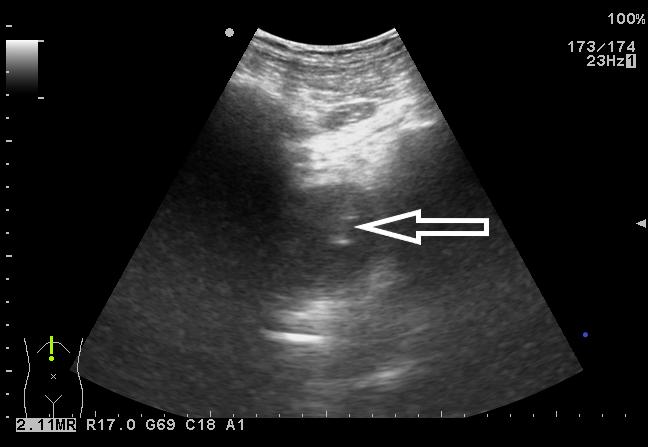

患者取俯卧位,充分暴露手术野,经臀超声扫查了解骶前脓肿情况,确定穿刺点,设计好穿刺路径。常规消毒铺巾,局麻,无菌保护套隔离探头。超声引导下PTC针穿刺直至脓腔边缘,迅速突破囊壁进入脓腔中心(图 3),退出针芯,外接注射器抽吸,见脓液流出(图 4)。将导丝通过针管插入脓腔,固定导丝,拔出针管,刀片沿导丝在臀部做2~3 mm小切口。插入扩张管扩张针道,经导丝将猪尾导管联合支撑管插入脓腔,超声确认穿刺到位(图 5)。拔出导丝,试抽有脓液流出,前推猪尾导管至其前端带侧孔段全部进入脓腔,拔出支撑管,可见液体流出。拉紧导管末端细线使导管尾端呈环状并固定,再次超声检查确定引流管在脓腔内(图 6),用缝线将引流管固定于皮肤上(图 7)。抽出约120 mL脓性液体,生理盐水反复冲洗脓腔,外接无菌引流袋。抽出的脓液取样送细菌培养,并做药物敏感实验。

|

| 图 3 超声引导下PTC针破壁进入脓腔 |